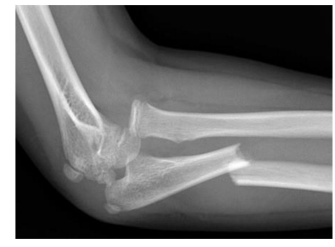

Na imagem da radiografia abaixo, temos uma fratura de Monteggia. Esta fratura está associada com: